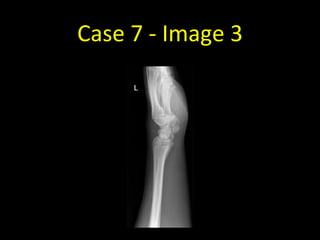

Case 7 - Image 3

Case 7

• Scaphoid fractures can be notoriously

difficult to see. Four views are obtained

when a scaphoid fracture is suspected.

• A comminuted fracture of the waist of

the left scaphoid is visible on this

scaphoid series - this example is easier

to spot than most scaphoid fractures

• If a scaphoid fracture is still suspected

despite not being visible on radiographs,

the wrist should be immobilised and

repeat radiographs performed in 7-10

days at which time the fracture may be

more apparent.